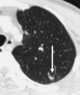

Renal cell carcinoma metastasis to lung

Renal cell carcinoma (RCC) is a kidney cancer that originates in the lining of the proximal convoluted tubule, a part of the very small tubes in the kidney that transport primary urine. RCC is the most common type of kidney cancer in adults, responsible for approximately 90–95% of cases. [Source: Wikipedia ]